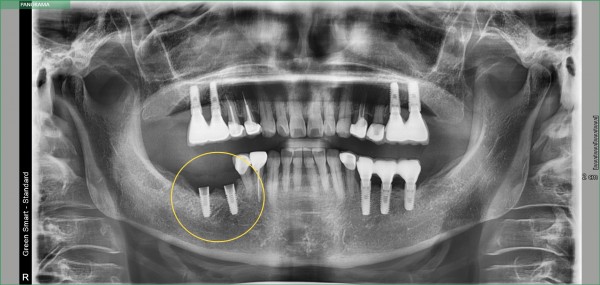

목록 글쓰기 임플란트 임플란트 재식립 사례 페이지 정보 작성자최고관리자 작성일2025-07-18 본문 타치과에서 실패한 임플란트 재식립 사례_365드림치과병원 댓글 0 댓글목록 등록된 댓글이 없습니다. 치료사례 카테고리 전체임플란트치아교정심미보철기타 Total 9건 1 페이지 게시물 검색 검색대상 제목+내용 제목 내용 작성자 검색어 필수 글쓰기 9 BEFORE AFTER 클릭 해주세요. 앞니 벌어짐 치아교정 8 BEFORE AFTER 클릭 해주세요. Smilefit 심미보철 심미보철 7 BEFORE AFTER 클릭 해주세요. Smilefit 심미보철 심미보철 6 BEFORE AFTER 클릭 해주세요. 전체교정 치아교정 5 BEFORE AFTER 클릭 해주세요. 전체치아교정 치아교정 4 BEFORE AFTER 클릭 해주세요. 전체 치아교정 치아교정 3 BEFORE AFTER 클릭 해주세요. 전체임플란트 임플란트 열람중 BEFORE AFTER 클릭 해주세요. 임플란트 재식립 사례 임플란트 1 BEFORE AFTER 클릭 해주세요. 하악 임플란트,치조골이식 임플란트 네이버 예약 협력기관 예약 MOU 카카오톡 상담 네이버 상담 + × TOP